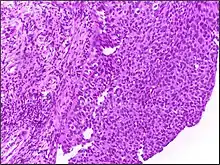

![]() | Small cell carcinoma of lung | Micograph of small Cell Carcinoma Lung. The tumor appears blue because the malignant epithelial cells are small with scanty cytoplasm, nuclei shows finely granulated chromatin. Cells are seen in clusters. There is nuclear overlapping with moulding and crushing. | Category: Histopathology of small cell lung cancer | Small cell lung cancer |